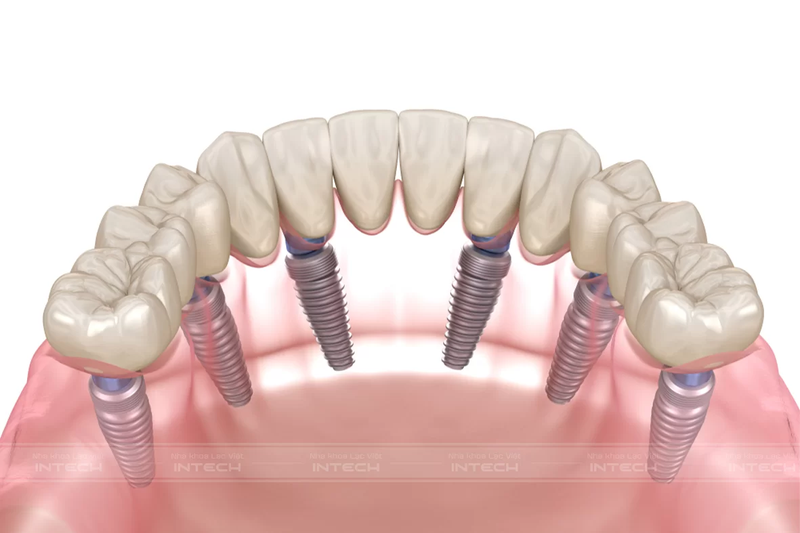

Trồng răng Implant All-On-6 sử dụng 6 trụ Implant cấy trực tiếp vào xương hàm tại các vị trí chiến lược để nâng đỡ một cầu răng sứ cố định phía trên và phân bổ lực nhai:

• 4 trụ Implant phía trước được cắm vào vùng răng cửa – nơi có mật độ xương hàm cao, giúp đảm bảo độ vững chắc.

• 2 trụ Implant phía sau được đặt ở vùng răng hàm, nghiêng một góc khoảng 30 – 45 độ để tăng khả năng chịu lực và hạn chế tác động tiêu cực lên xoang hàm (ở hàm trên) hoặc dây thần kinh (ở hàm dưới).

Sau khi trụ Implant tích hợp vững chắc với xương hàm, bác sĩ sẽ lắp cầu răng sứ (Dental Bridge) gồm 14 răng lên trên để tái tạo hoàn chỉnh cung răng. So với phương pháp trồng răng truyền thống yêu cầu cấy ghép từng trụ Implant cho mỗi răng mất, All-On-6 tối ưu hơn về số lượng trụ nhưng vẫn đảm bảo độ ổn định và khả năng chịu lực lâu dài.

Kỹ thuật trồng răng Implant All-On-6 sử dụng 6 trụ Implant để nâng đỡ một hàm giả